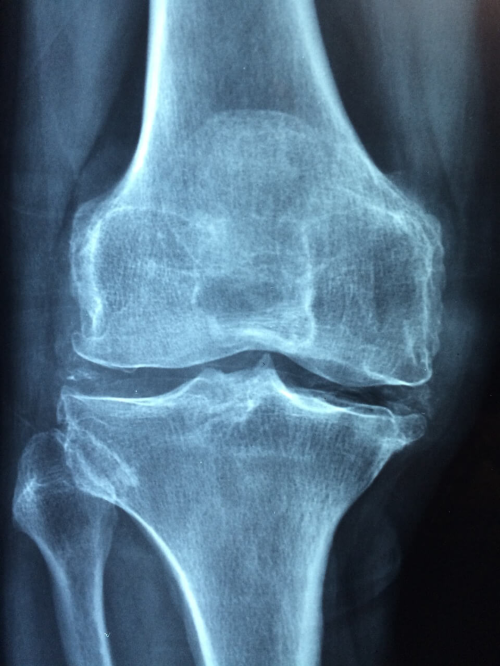

움직일 때 관절에서 ‘딱’, ‘뚝’ 소리가 나고, 심하면 통증까지 느껴진다면 퇴행성 관절염의 초기 징후일 수 있습니다.

연골이 닳아 관절 사이가 부딪히며 생기는 소리일 가능성이 높습니다.

퇴행성 관절염은 특히 계단을 오르거나 앉았다 일어날 때 통증이 심해지는 특징이 있습니다.

이유는 무릎에 하중이 집중되면서 닳은 연골이 마찰을 일으키기 때문이죠.

걸을 때보다 계단에서 더 아프다면, 연골 손상이 시작된 것일 수 있습니다.

퇴행성 관절염은 시간이 지날수록 진행되며, 연골 손상이 누적되면 수술까지 필요한 경우도 있습니다.